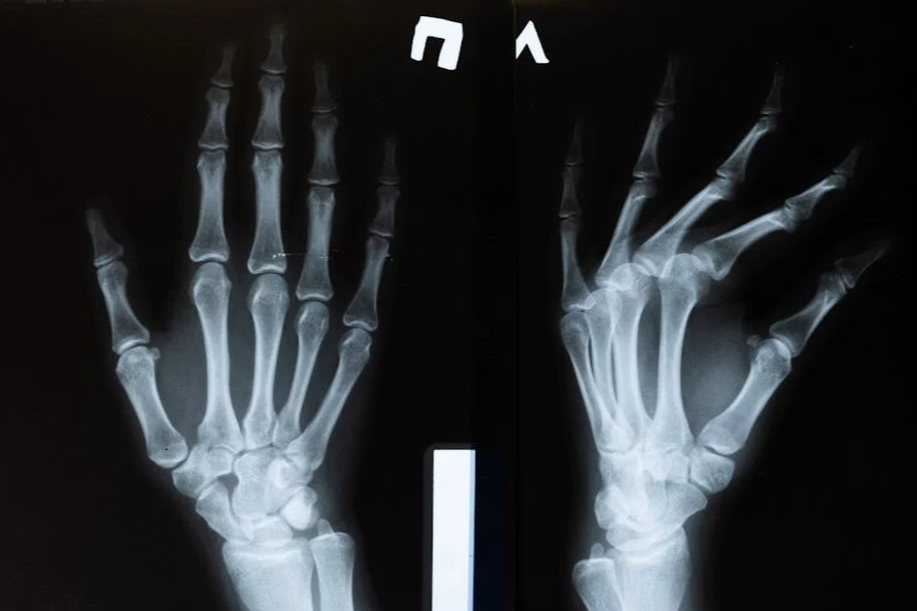

습관성 탈골이란?

습관성 탈골은 관절이 한 번 탈골된 이후, 반복적으로 같은 부위의 탈골이 발생하는 상태를 말합니다. 주로 어깨 관절에서 많이 발생하지만, 턱, 무릎, 손가락 등 다양한 관절에서도 나타날 수 있습니다. 처음 탈골이 생겼을 때 제대로 된 치료가 이루어지지 않으면 관절의 안정성이 떨어지면서 습관적으로 빠지는 현상이 나타나게 됩니다.

4. 수술적 치료

반복적인 탈골로 관절 구조가 심하게 손상된 경우에는 관절을 재구성하는 수술이 필요할 수 있습니다. 대표적인 수술로는 관절낭 봉합술이나 관절경을 이용한 관절 안정화 수술 등이 있습니다.